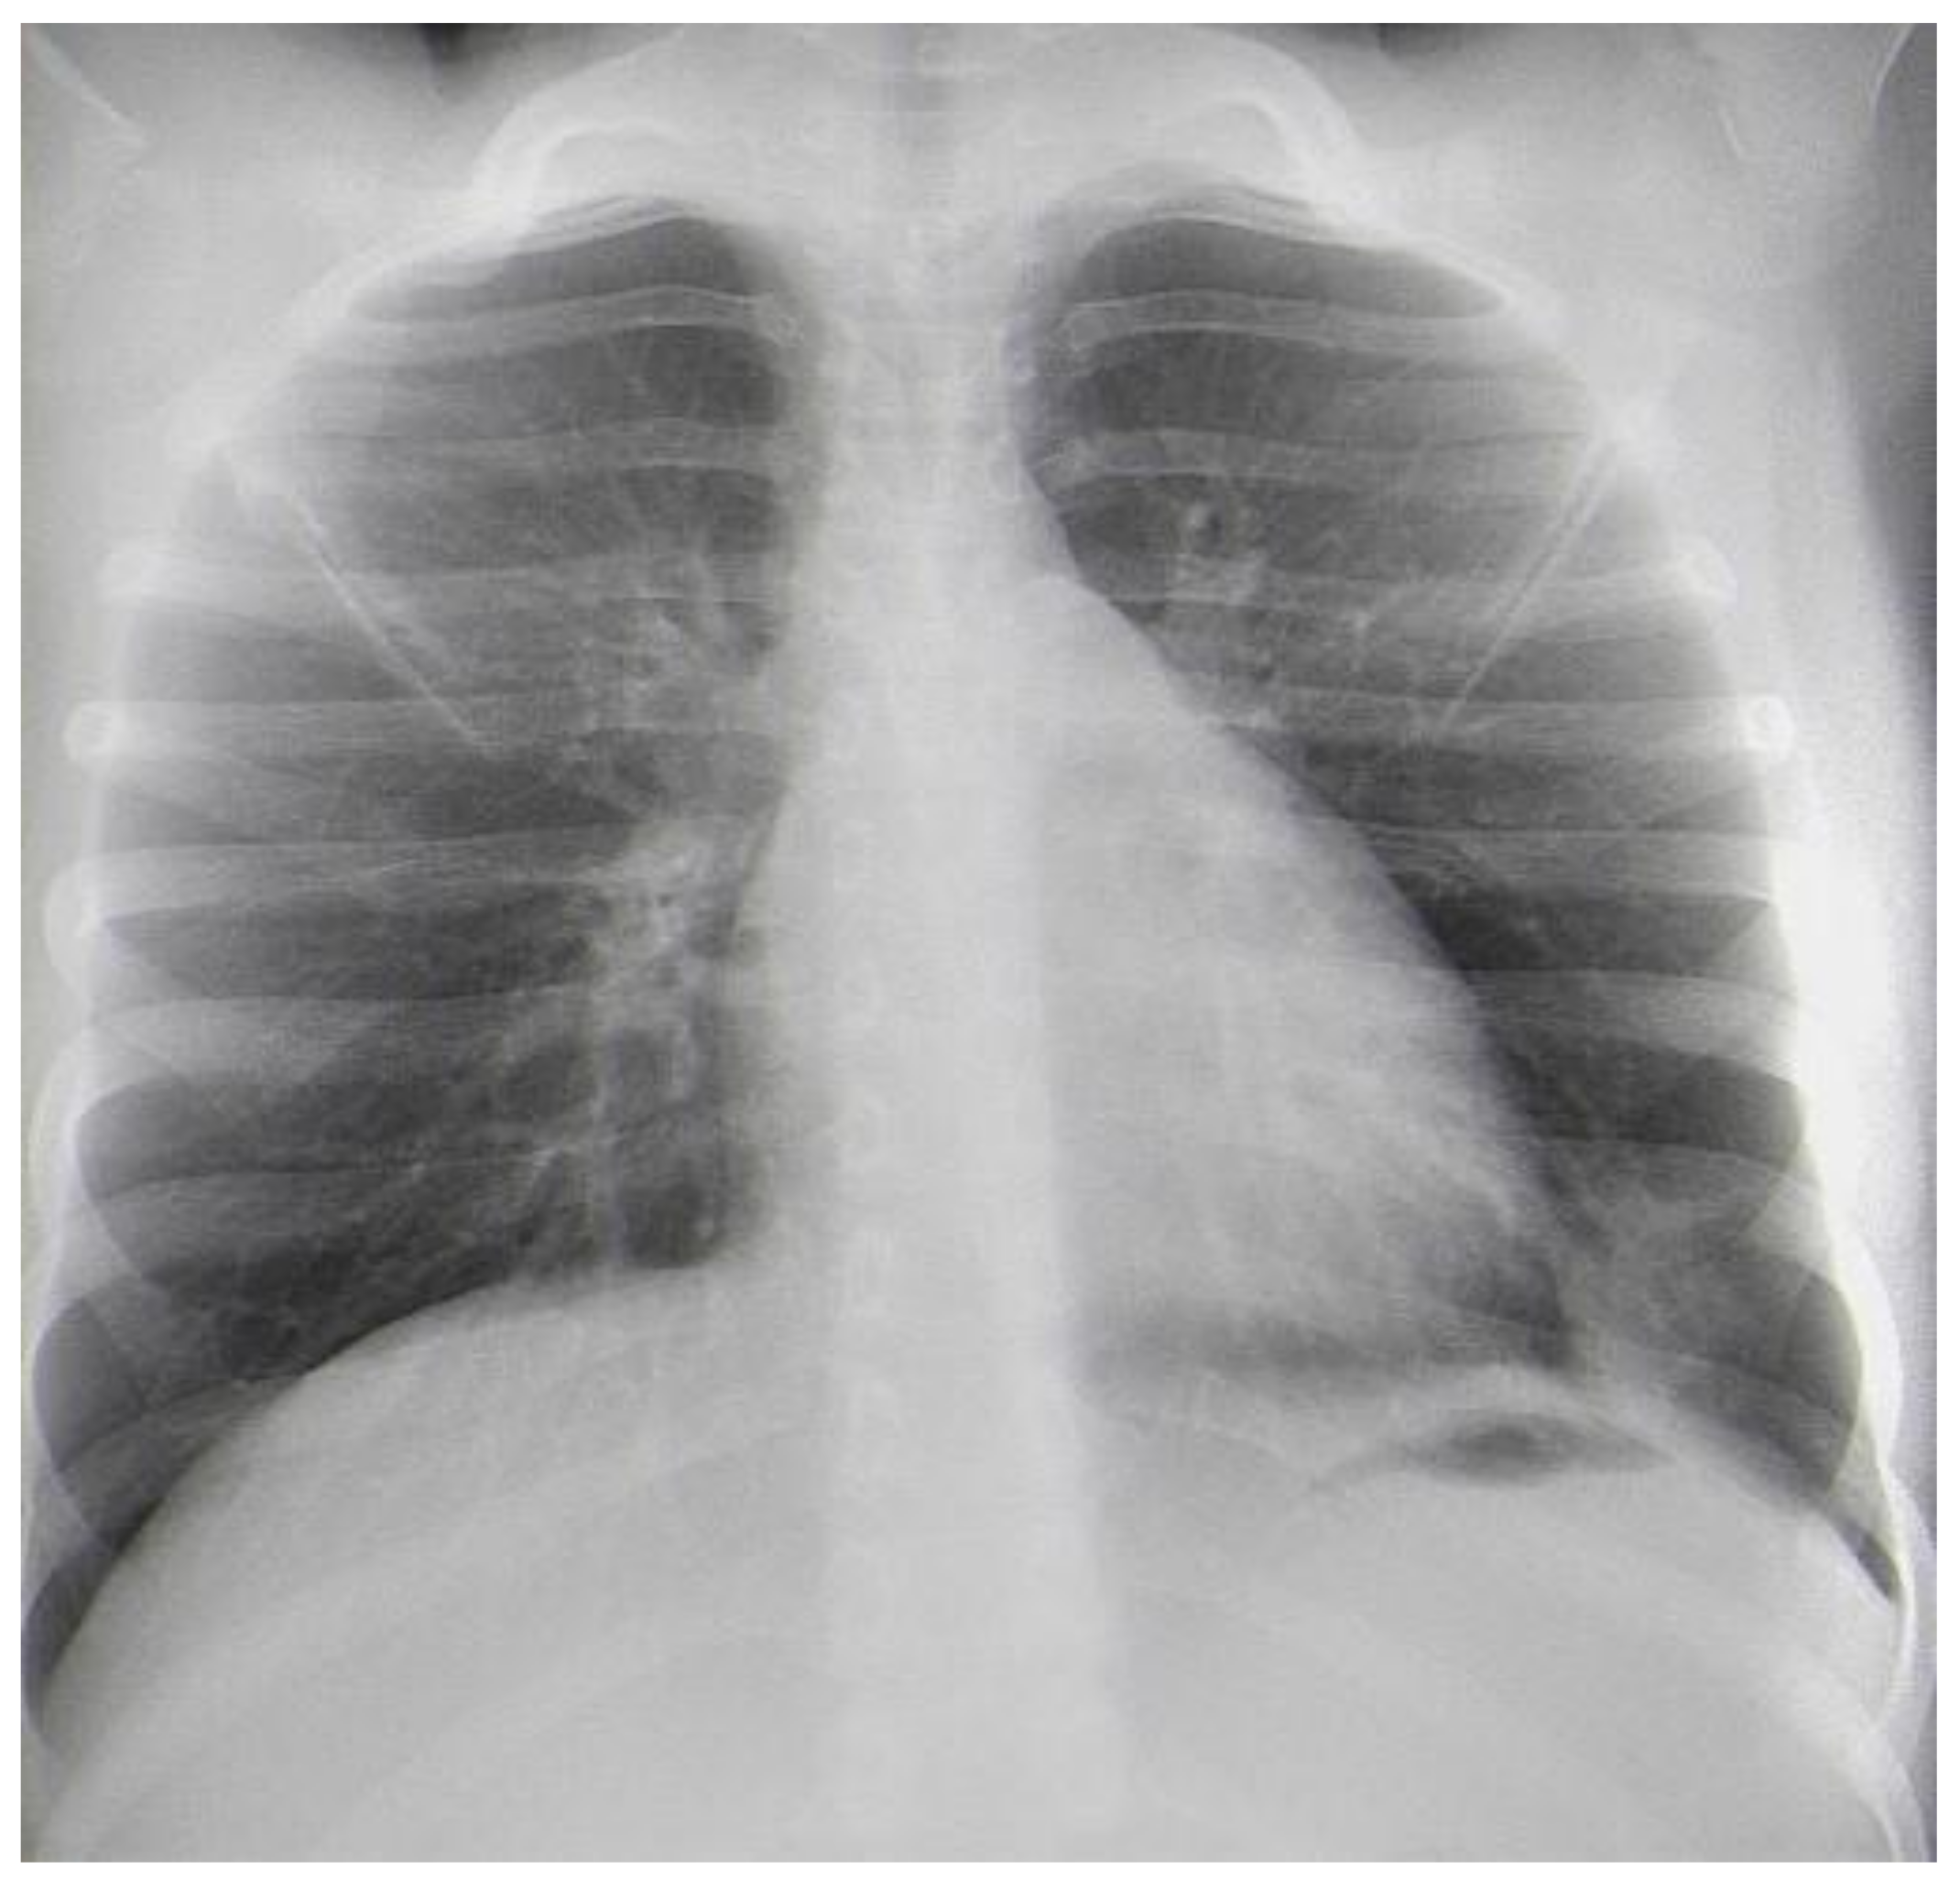

We present a 9-year-old boy with a history of recurrent respiratory infections. In July 2022, the child swallowed an awn during a walk on a field in Northwest Bulgaria, and after two days, he started to cough. On the third day after the accident, he became febrile, and antibiotic therapy was prescribed (Clarithromycin). This treatment was not effective, and the child suffered left-sided chest pain, irradiating to his left shoulder. Nonsteroidal anti-inflammatory drugs were prescribed. On the 10th day, the patient was admitted to the Department of Pediatric Pulmonology for further diagnostic workup and treatment. The child’s condition was stable, with a productive cough and reduced vesicular breathing paravertebrally and axillary on the left side of the chest. His hemodynamic was stable, and his abdomen was not tender, without hepatosplenomegaly. His blood tests showed inflammation—increased C-reactive protein (CRP) 36.29 mg/L and leukocytes 10,9 x109 L, and stable hematological parameters (hemoglobin 126 g/L, hematocrit 39%, erythrocytes count range 4.69, platelets 347). Biochemical markers were also in the normal range—sugar level 6.08 mmol/L, creatinine 42 µmol/L, urea 2 mmol/L, ASAT 15 U/L, ALAT 12 U/L, alkaline phosphatase 127 U/L, total protein 65.3 g/L, albumin 41.26 g/L. Frontal and lateral chest X-rays showed faint reticular and patchy opacities with unclear margins in the lower lobe of the left lung (Figure 1A,B). Treatment comprised antibiotics (Ceftriaxone), corticosteroids (Methylprednisolone), and saline inhalations.

Figure 1. (A). Frontal chest X-ray—faint reticular and patchy opacities with unclear margins were visualized in the lower lobe of the left lung. (B). Lateral chest X-ray.